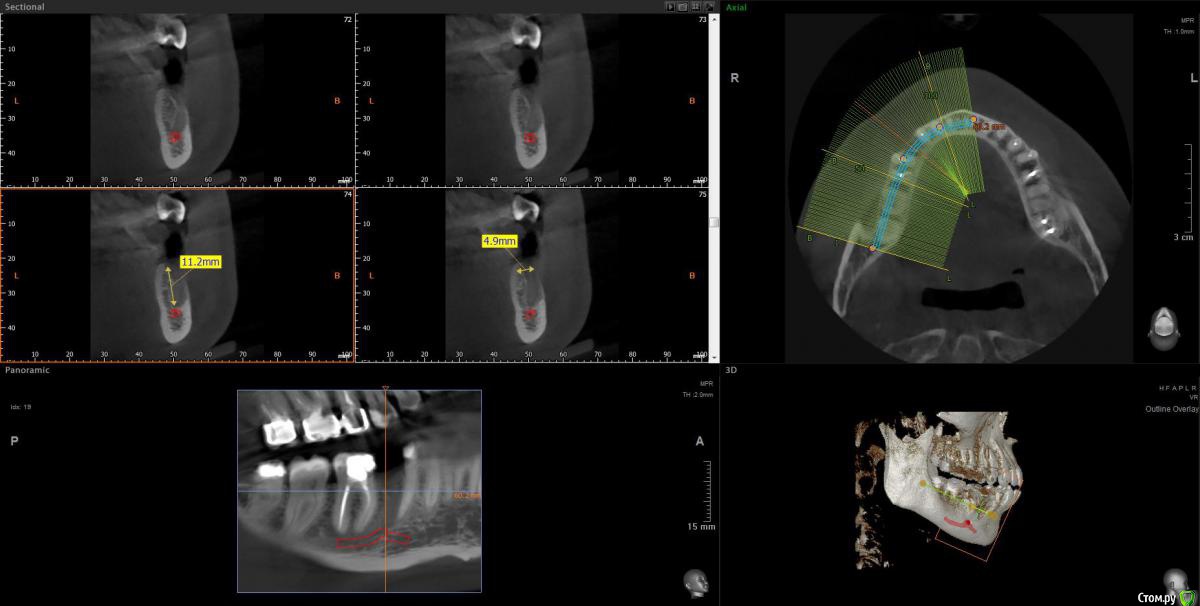

Cleo15 Опубликовано 26 мая, 2020 Поделиться Опубликовано 26 мая, 2020 Добрый день!После удаления нижней пятерки имплантолог на консультации сказал, что корень соседней четверки растет так, что у нас 2 варианта имплантации: либо ставить длинный под наклоном, либо рискнуть установить короткий (10 мм.) вертикально.При этом конструкция под наклоном не столь надежна, как вертикальная вследствие предстоящих проблем с абатментом, а при вертикальной установке существует риск повреждения корня четверки (который я должна взять на себя, следует заметить) плюс долговечность имплантата вследствие его малости также под вопросом.Подскажите, пожалуйста, какой метод предпочтительнее выбрать в такой ситуации? Ссылка на комментарий

Irouil Опубликовано 26 мая, 2020 Поделиться Опубликовано 26 мая, 2020 (изменено) 10 мм - это не короткий имплантат, нужно смотреть КТ, но по этому снимку никаких явных проблем с установкой имплантата я не вижу Зуб давно удалён? Изменено 26 мая, 2020 пользователем Irouil 1 Ссылка на комментарий

Cleo15 Опубликовано 26 мая, 2020 Автор Поделиться Опубликовано 26 мая, 2020 Удален 5 месяцев назад.КТ https://my-files.su/2kio3d Ссылка на комментарий

krokomot Опубликовано 26 мая, 2020 Поделиться Опубликовано 26 мая, 2020 можно и 8мм поставить это не принципиально Ссылка на комментарий

stommm Опубликовано 27 мая, 2020 Поделиться Опубликовано 27 мая, 2020 10мм имплант в правильной ортопедической позиции предпочтительнее 14 мм импланта в неправильной. И 10 это не короткий. И 8 мм нормальный размер. Короткий это 4 мм длина. Ссылка на комментарий

Bier Опубликовано 28 мая, 2020 Поделиться Опубликовано 28 мая, 2020 таки правильно тут ставить с небольшим наклоном. Длина не имеет значения. Ссылка на комментарий